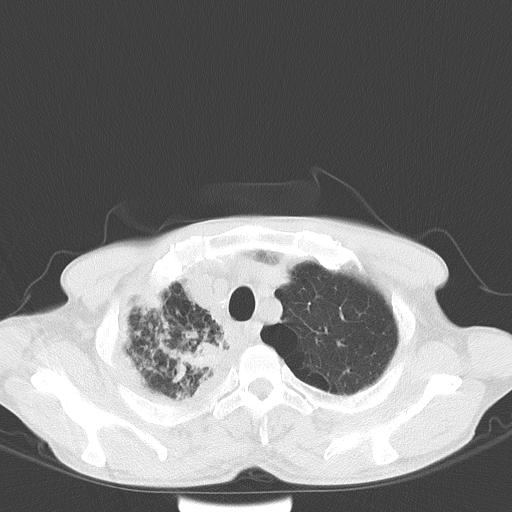

男性 75  咳嗽 一周前发热最高达39

右肺继发型tb并右侧tb性胸腔炎,右侧胸腔大量积液并右下肺膨胀不全,慢支肺气肿、多发肺大泡。建议抽胸水实验室检查并复查排除恶性在占位。

右上肺继发型肺结核,右胸腔中等量积液。

左上肺大泡。

结核的基础上有纵隔淋巴结肿大,右侧有胸水,但右侧纵隔反而窄,说明有肺有不张。

再就是右下肺有块影,和不张混合,还是不能除外肺癌。

补充材料,患者2月份ct片大致正常,双侧胸腔积液,2月份抽胸水未发现ca细胞,现患者发热,痰多,各气管通畅,

1)右肺继发型肺结核。2)左肺胸膜下多发性肺大泡。3)右侧胸腔积液。